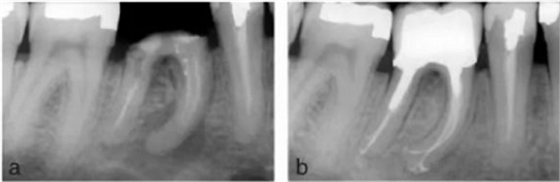

在白種人中,下頜第一磨牙主要為雙根—近中根和遠(yuǎn)中根,但其中根管形態(tài)各異。根據(jù)Vertucci 的分類,下頜第一磨牙中 59%的近中根在根尖處為獨(dú)立的雙根管,28%為兩根管融合成單根管單根尖孔,12%為單根管,1%為三根管(8,9)(圖 11a,b)。在另一項(xiàng)研究中,下頜磨牙的近中中根管(MM)發(fā)生率在 1%至 7%之間變化(92-99)。三個(gè)近中根管可以是獨(dú)立的(92-95)或融合稱為兩個(gè)根管,在根尖有兩個(gè)根管口(96-99)。